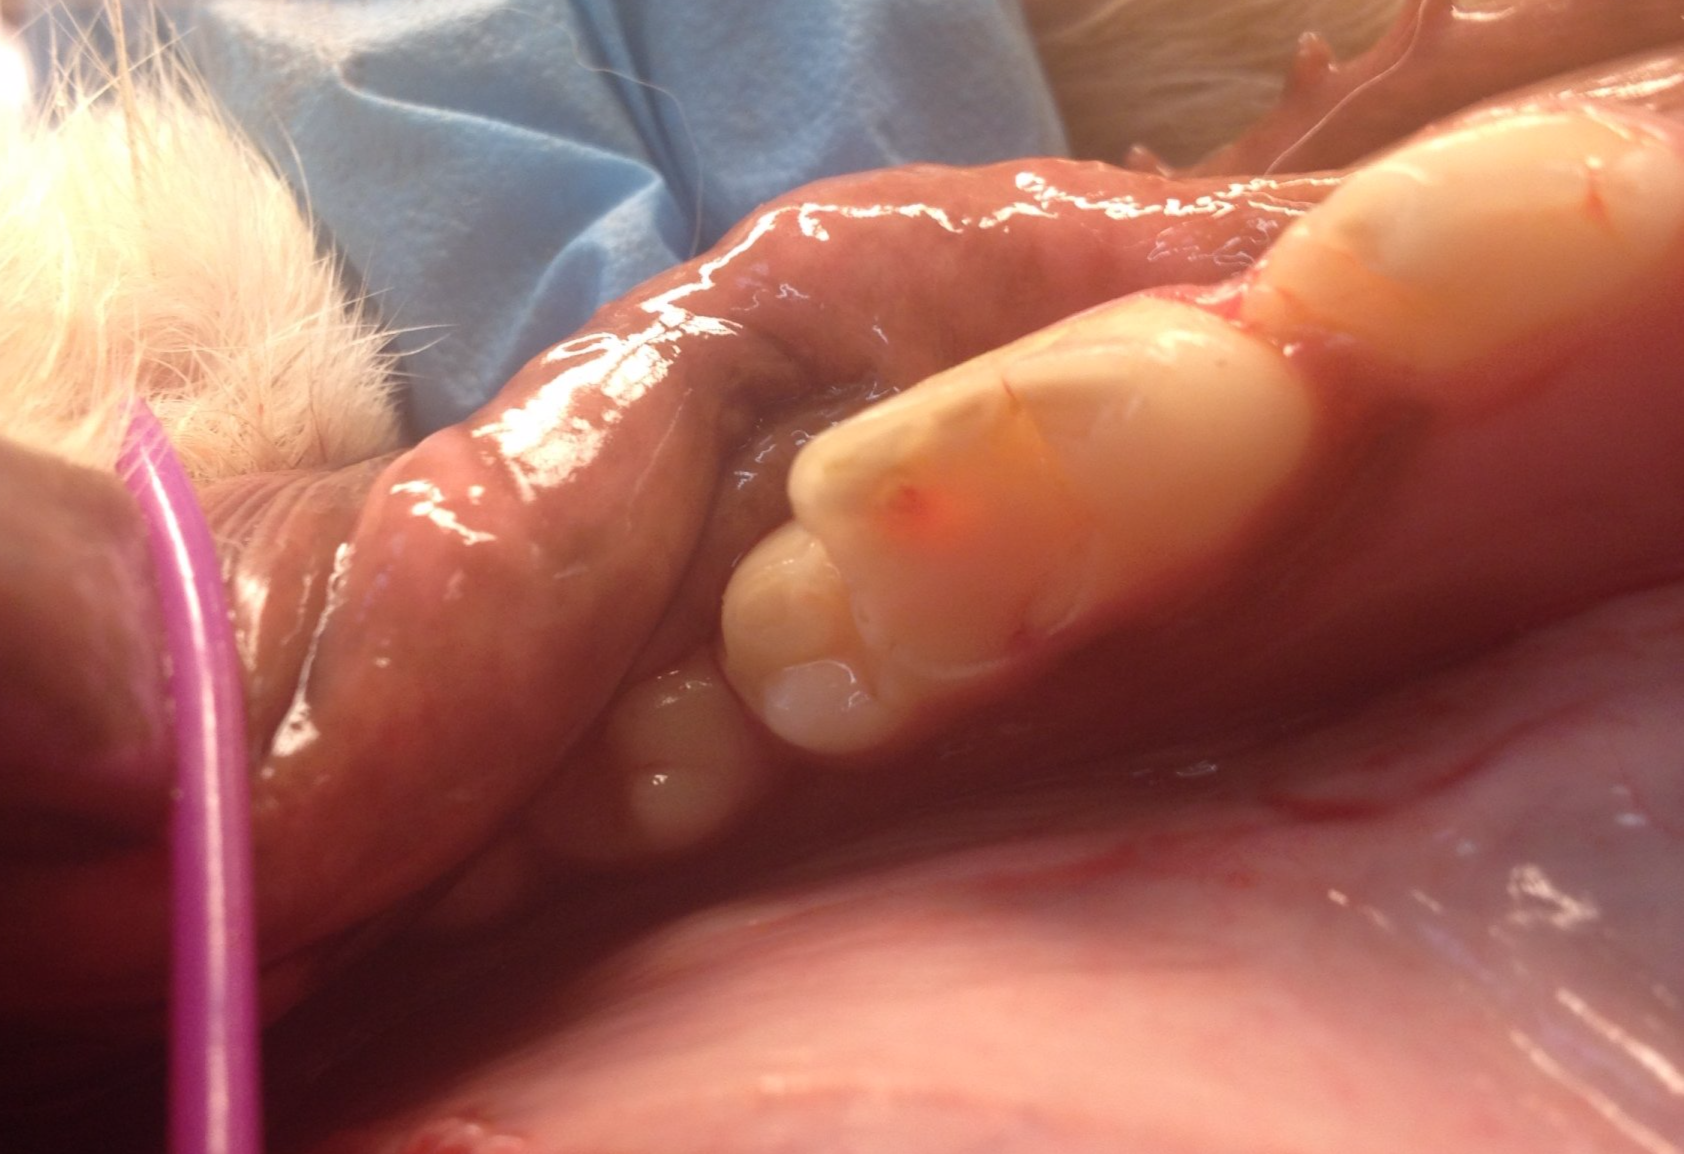

Een hond met ernstige Parodontitis

Op foto 1 en 4

zie je de kiezen in de kaak, ogenschijnlijk nog mooie elementen om te zien, maar

Op foto 3

zie je het resultaat na extractie van de kiezen van de linkerbovenkaak.

Extra:

Deze hond heeft een ernstige vorm van parodontitis (ontsteking van het weefsel rondom een kies of tand) en is ooit begonnen als een gingivitis (tandvleesontsteking). Door het langdurig aanwezig zijn van een ontstekingsreactie door tandplaque is het bot langzaam weggetrokken. Deze chronische ontsteking is zeer pijnlijk en ook gevaarlijk voor andere organen in het lichaam. Preventie door poetsen en goede, regelmatige tandheelkundige behandelingen is de oplossing dit te voorkomen. Welke regelmaat van behandelingen nodig is, is per dier verschillend.